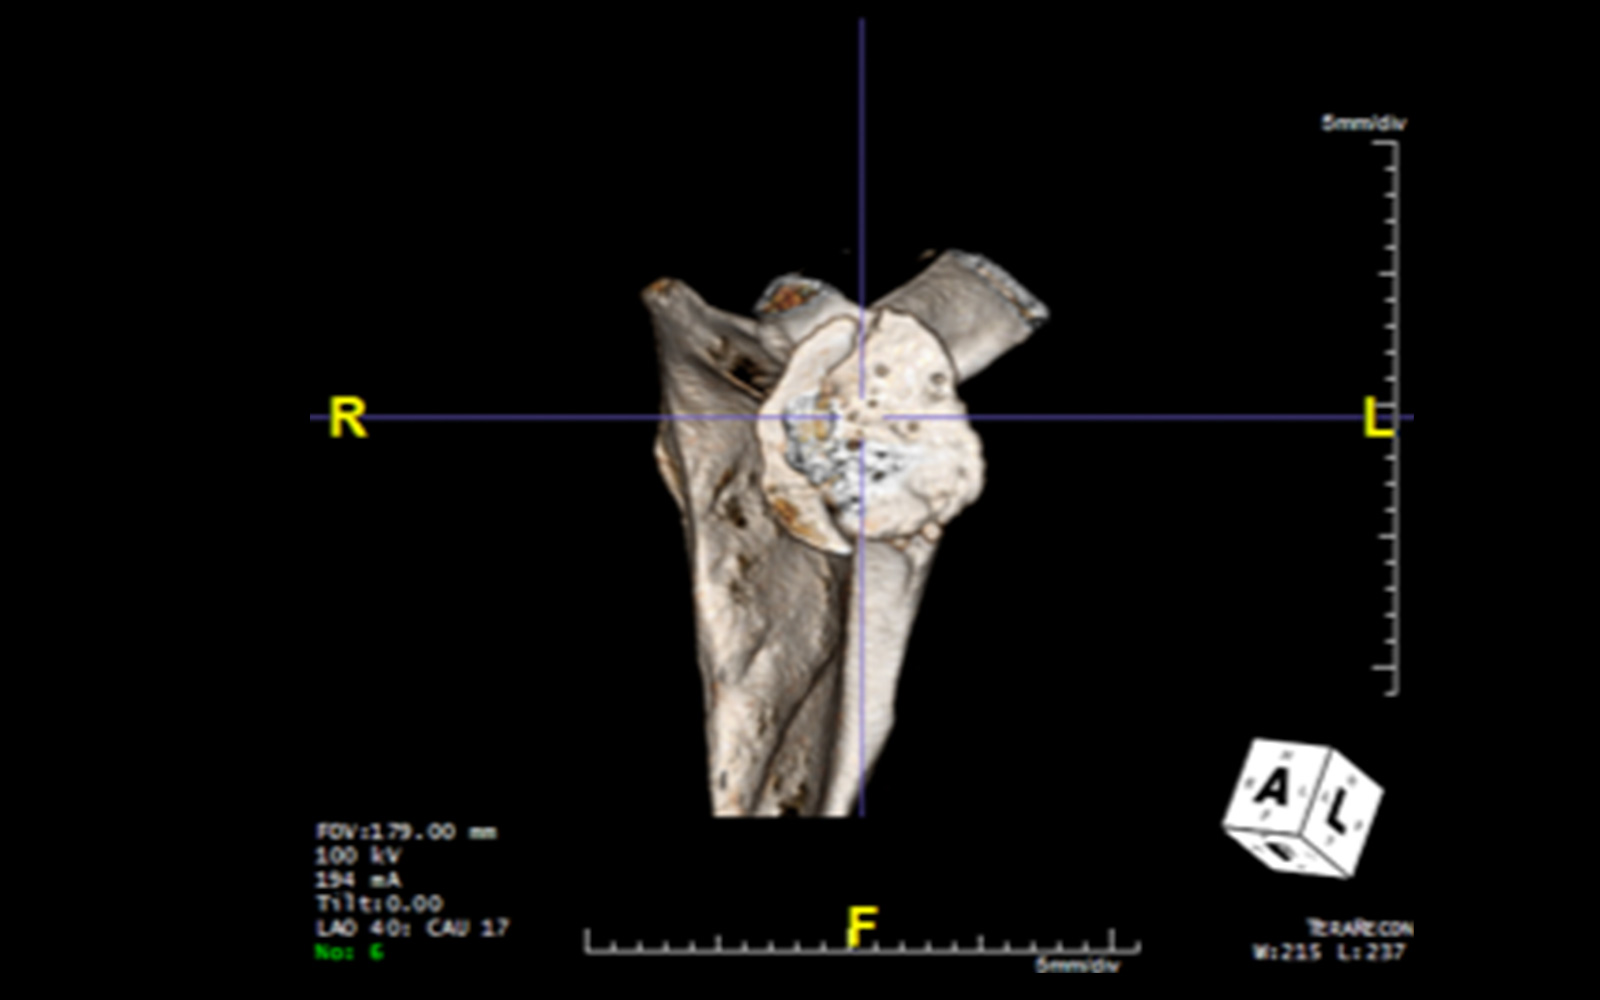

Patient-Specific Guides With a Custom Implant: Is This a Practical Solution?